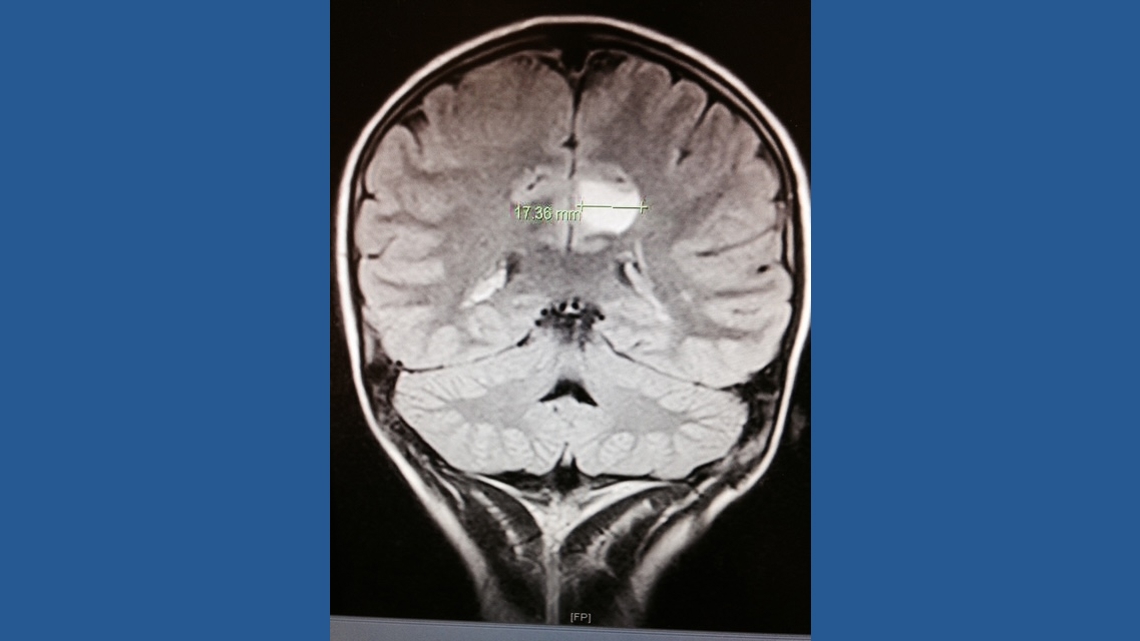

ATLANTA — Holland Chandler was just 11 years old when a concussion at school led to a discovery that would change her life: a small, benign tumor on her brain.

“At first, there was a small little blemish on the scan, and we didn’t understand what it was, what it meant, or what to do about it, really,” said pediatric neurosurgeon Dr. Andrew Reisner. “That little spot on the CT scan was of enough concern that we wanted to follow it.”

For three years, Dr. Reisner monitored the tumor.

By the time Holland was 14, it had grown enough to require surgery.